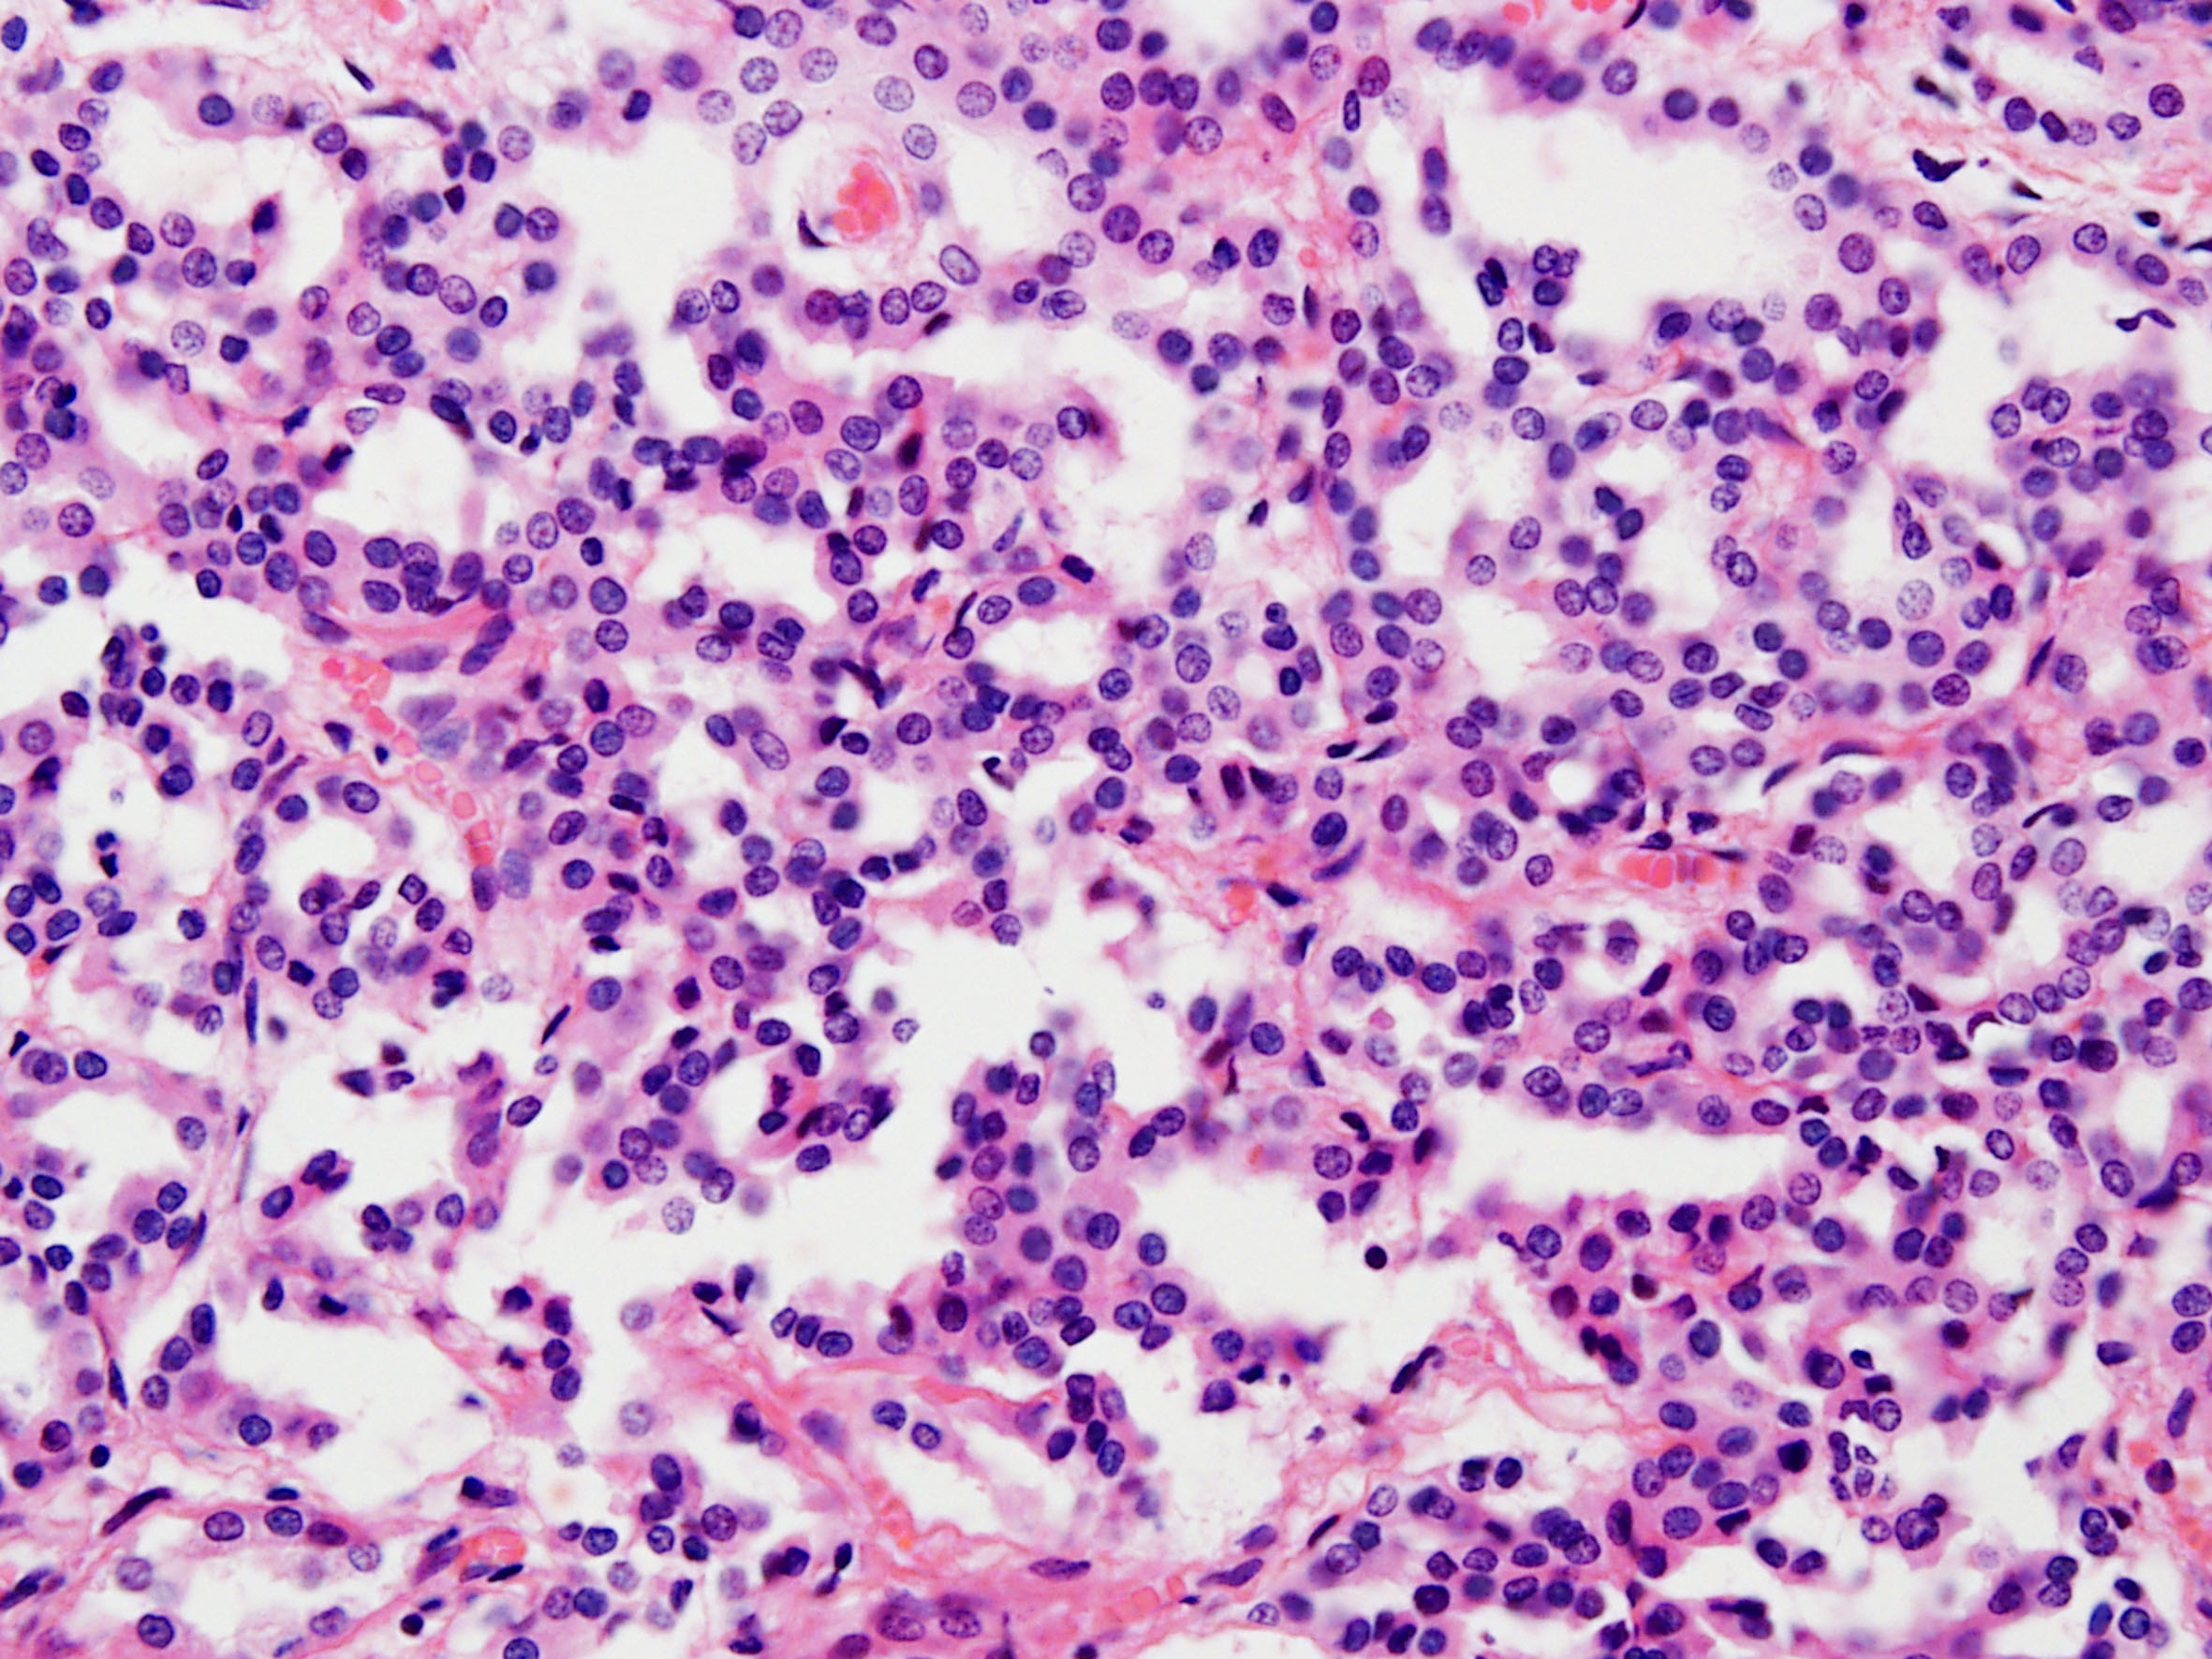

Case description (by case creator):

Papillary adenoma